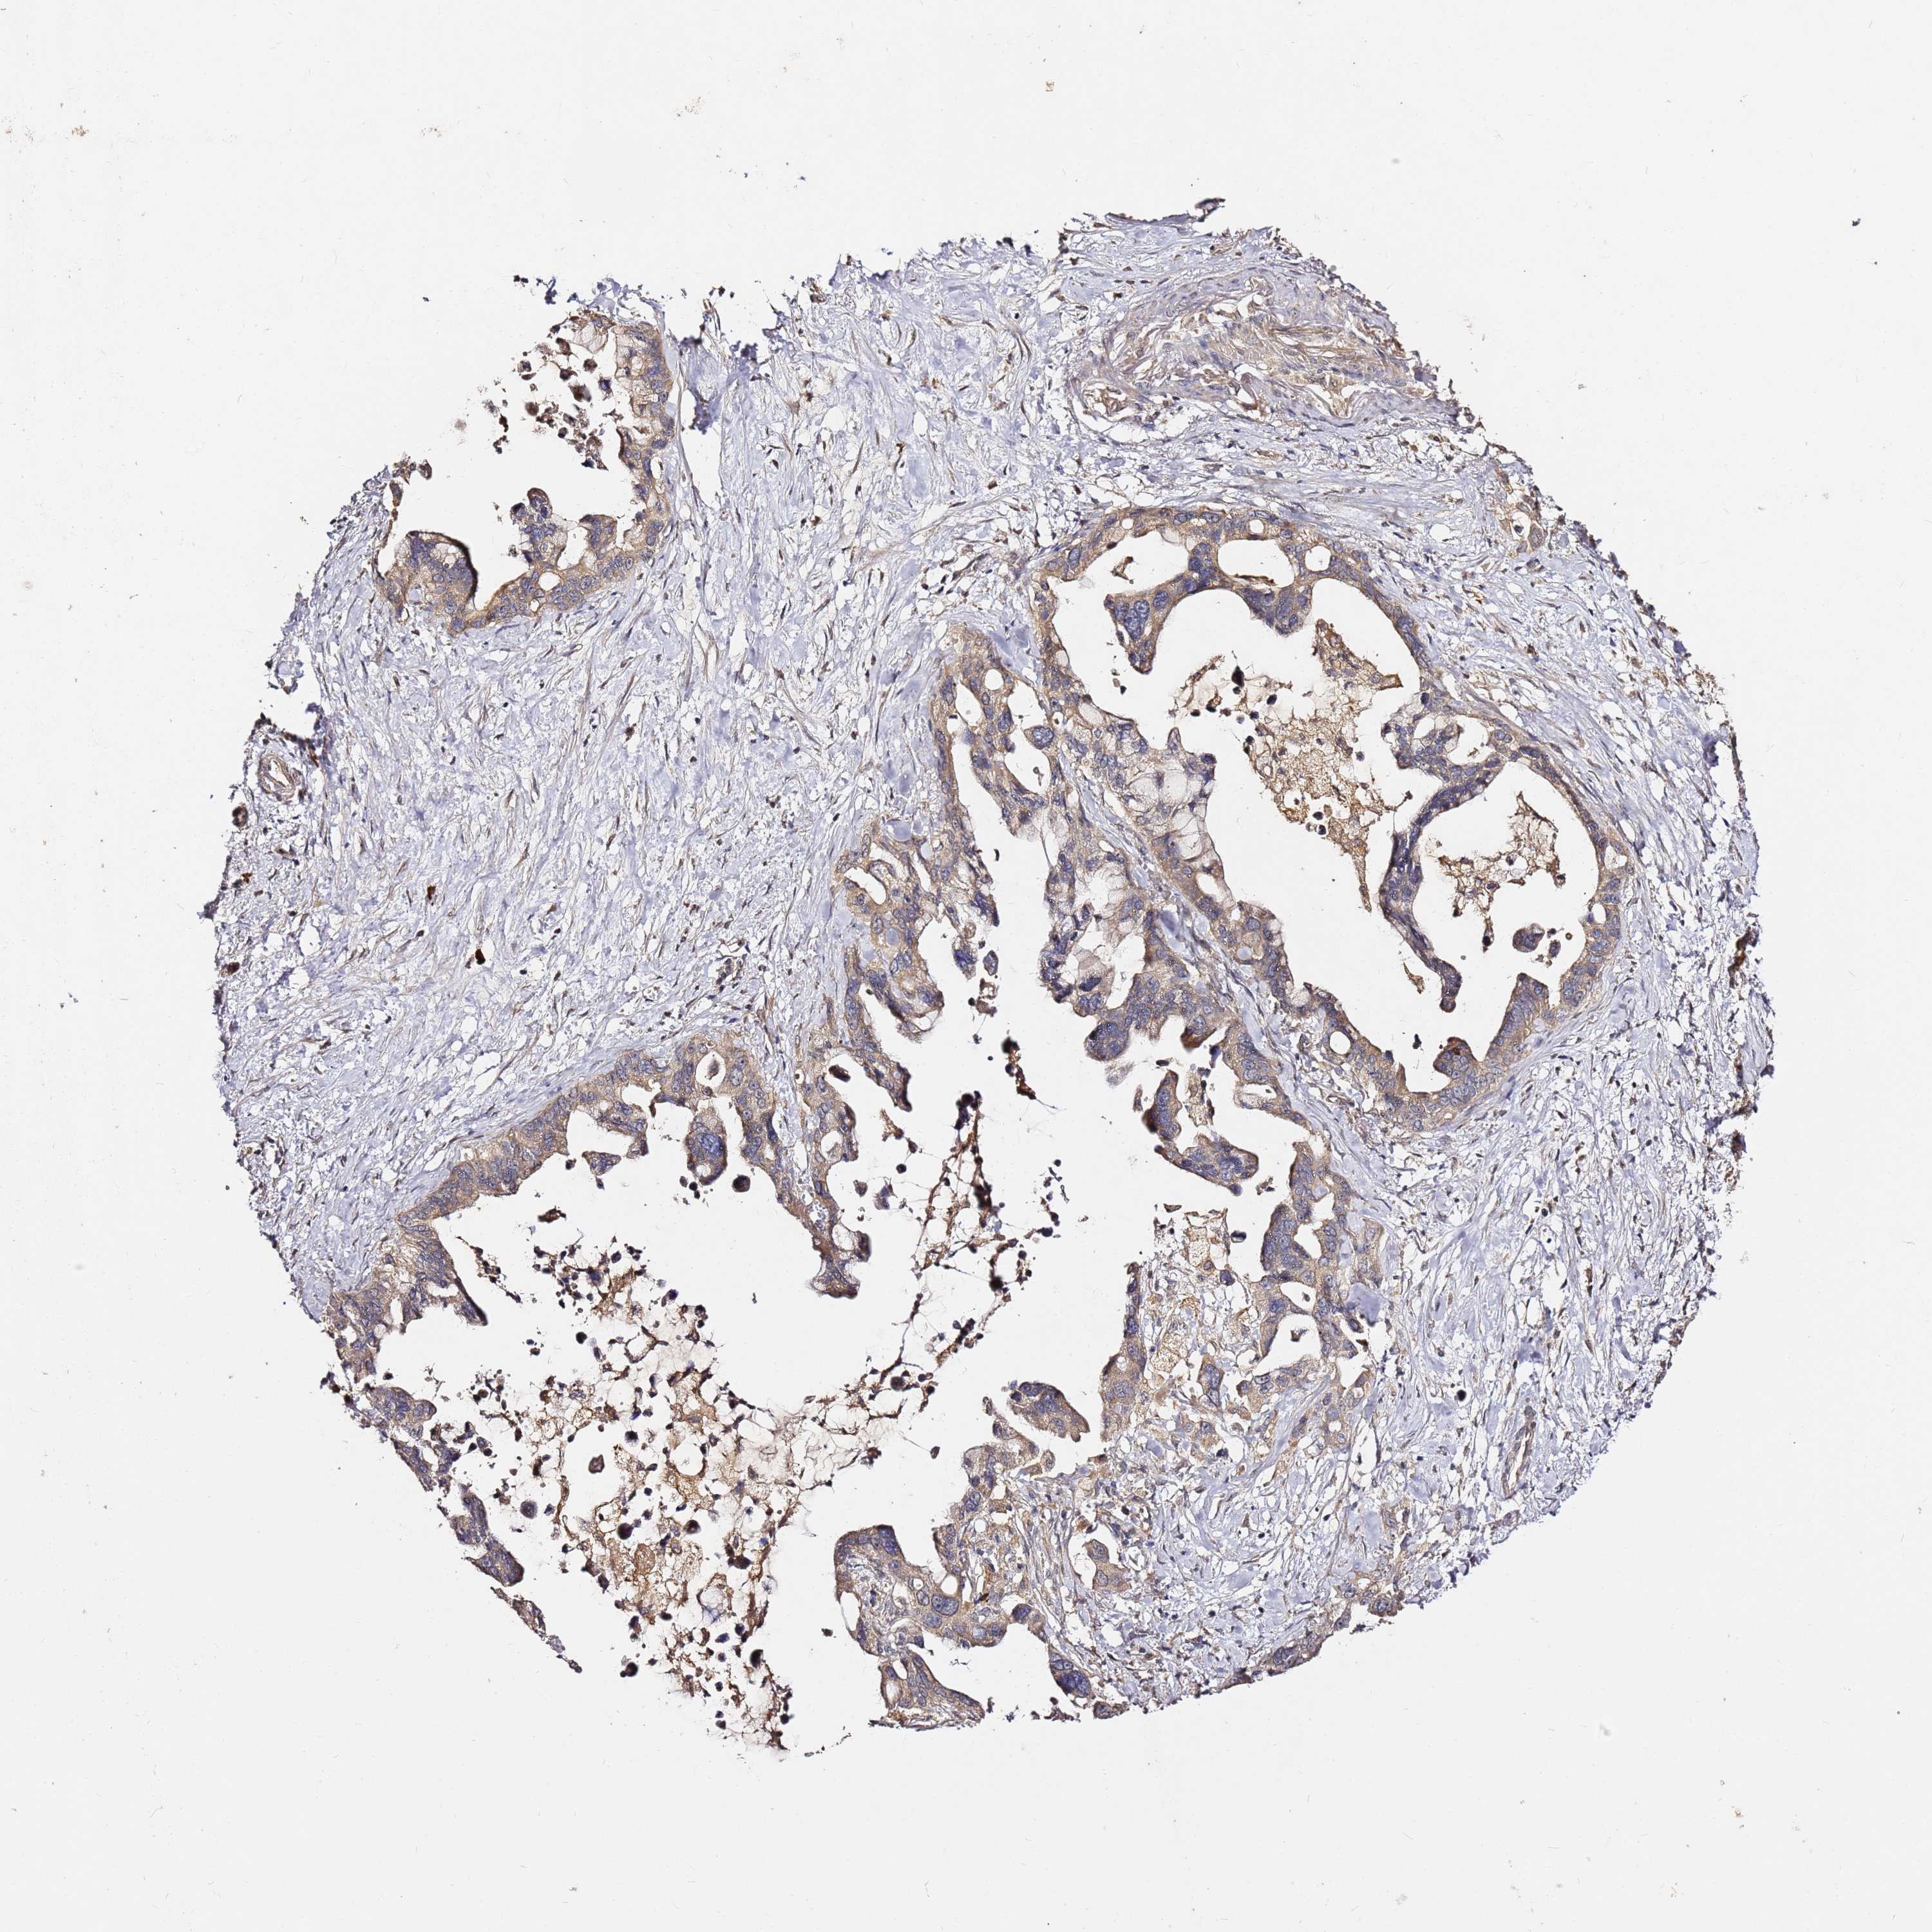

PANCREATIC CANCER - Protein expressioni

A mouse-over function shows sample information and annotation data. Click on an image to view it in a full screen mode. Samples can be filtered based on level of antibody staining by selecting one or several of the following categories: high, medium, low and not detected. The assay and annotation is described here.

Note that samples used for immunohistochemistry by the Human Protein Atlas do not correspond to samples in the TCGA dataset.

Antibody stainingi

Antibody staining in the annotated cell types in the current human tissue is reported as not detected, low, medium, or high, based on conventional immunohistochemistry profiling in selected tissues. This score is based on the combination of the staining intensity and fraction of stained cells.

Each image is clickable and will lead to virtual microscopy that enables deeper exploration of all samples and also displays staining intensity scores, fraction scores and subcellular localization as well as patient and tissue information for each sample.

Antibody HPA046804

Staining

High

Medium

Low

Not detected

Intensity

Strong

Moderate

Weak

Negative

Quantity

>75%

75%-25%

<25%

None

Location

Nuclear

Cytoplasmic/membranous

Cytoplasmic/membranous,nuclear

Adenocarcinoma, NOS